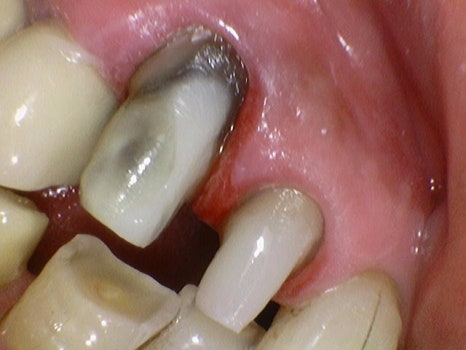

치아가 검은색으로 변색은 되었지만 충치가 진행된 부위가 아닌

양호한 부위는 보존하고

크라운의 유지력을 위해 치아를 다듬고 난 후 크라운을 다시 부착하였습니다.

발치도 고민을 했었던 치아이지만

중요한 기능을 하고 있는 송곳니이기 때문에

유지하는 편이 좋다고 판단하여

최대한 써보기로 말씀드렸습니다.

이 케이스는 운이 좋게도

치아머리 부분이 조금 남아 있어서

치아를 보강한 후 보철까지 할 수 있었습니다.